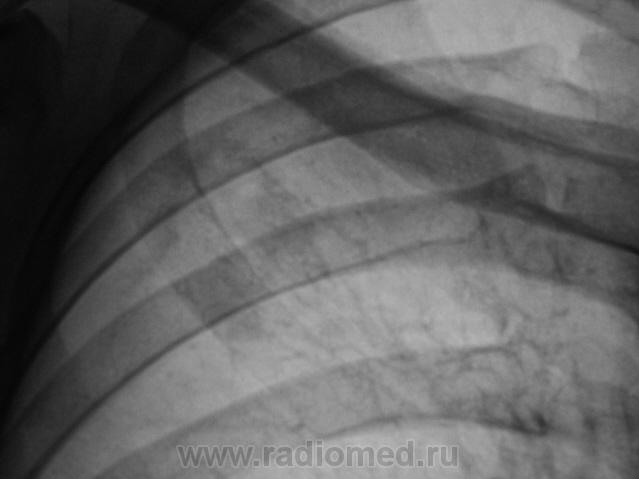

Я бы остановилась на множественных туберкулемах s1-2 обоих легких,Туберкулемы не однородны.за счет уплотнения,пл очаги.фиброз.

Слева туберкулома и корень подтянут Справа-очаги отсева .Динамика типичная- лечим.лечим-а туберкуломе хоть бы хны!

Туберкулёма только в С1+2 слева, как дела давно минувших дней.  Произошла реактивация туберкулёзного процесса с развитием двустороннего очагового туберкулёза. Имеется положительная динамика в виду некоторого уплотнения очагов. Таково мое мнение.